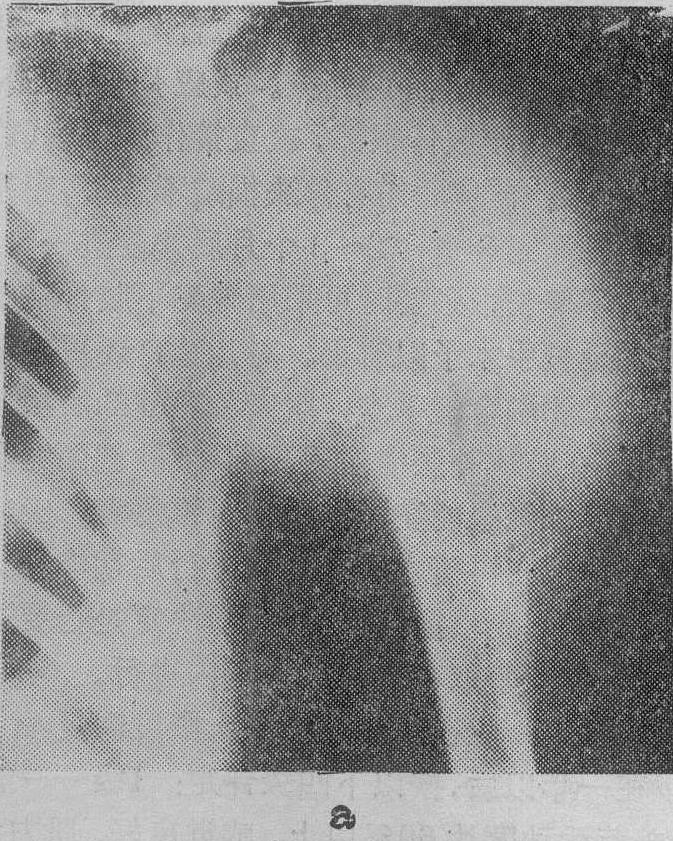

早在1903年,Hopfner就进行了狗腿切断再植的动物实验,但未得到预期的结果。1906年Carrel等首先成功地再植了一只狗的后腿。1953年,Лапчинский也获得狗腿再植成功。1960年,我国屠开元等也进行了狗腿完全断离再植的动物实验,并取得成功的经验。1962年12月Soupault曾报道2例不全断离的上肢再植,其中1例失败,1例功能恢复欠佳。1963年,我国陈中伟等首次报道了1例前臂完全性创伤性断离的病例,经再植成功,并恢复了良好的功能(图1)。不久以后,Shorey和Malt也分别报道了他们在1962年再植成功的2例上肢完全断离的病例。此后,国内、外对完全和不全断离再植的报道渐见增多。至今,以我国报道的病例数为最多,而且对于用多接静脉来减轻肢体肿胀,早期修复神经促使功能尽早恢复,用冷藏和高压氧治疗来延长肢体耐受缺血时限,肢体的移位再植,以及用段截与再植来治疗上肢恶性肿瘤等方面,积累了丰富的经验。

图1 右前臂完全断离,再植成功

a. 再植前 b. 再植后一年,已恢复原工作